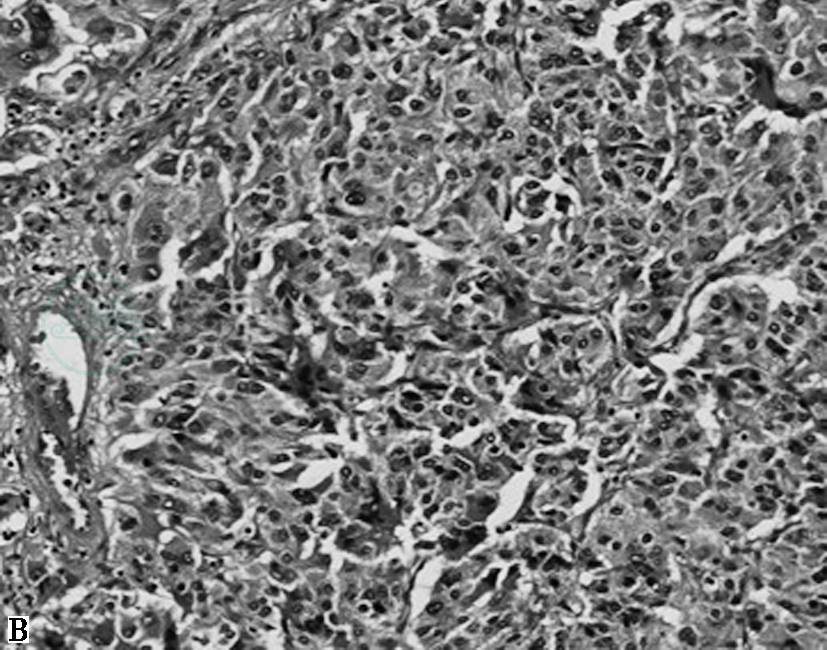

图1嗜铬细胞瘤镜下表现

A.HE 60倍,肿瘤周围见受压的肾上腺皮质;B.HE 100倍,特征性巢状(Zellballen结构),周围包绕纤细的纤维血管性间质;C.HE 200倍,肿瘤细胞形状和大小变化大,嗜碱性或嗜双色性,核仁明显,可见细胞核假包涵体及胞质玻璃样小体;D.HE 200倍,肿瘤细胞多形性及核深染明显,可见胞质内透明小球